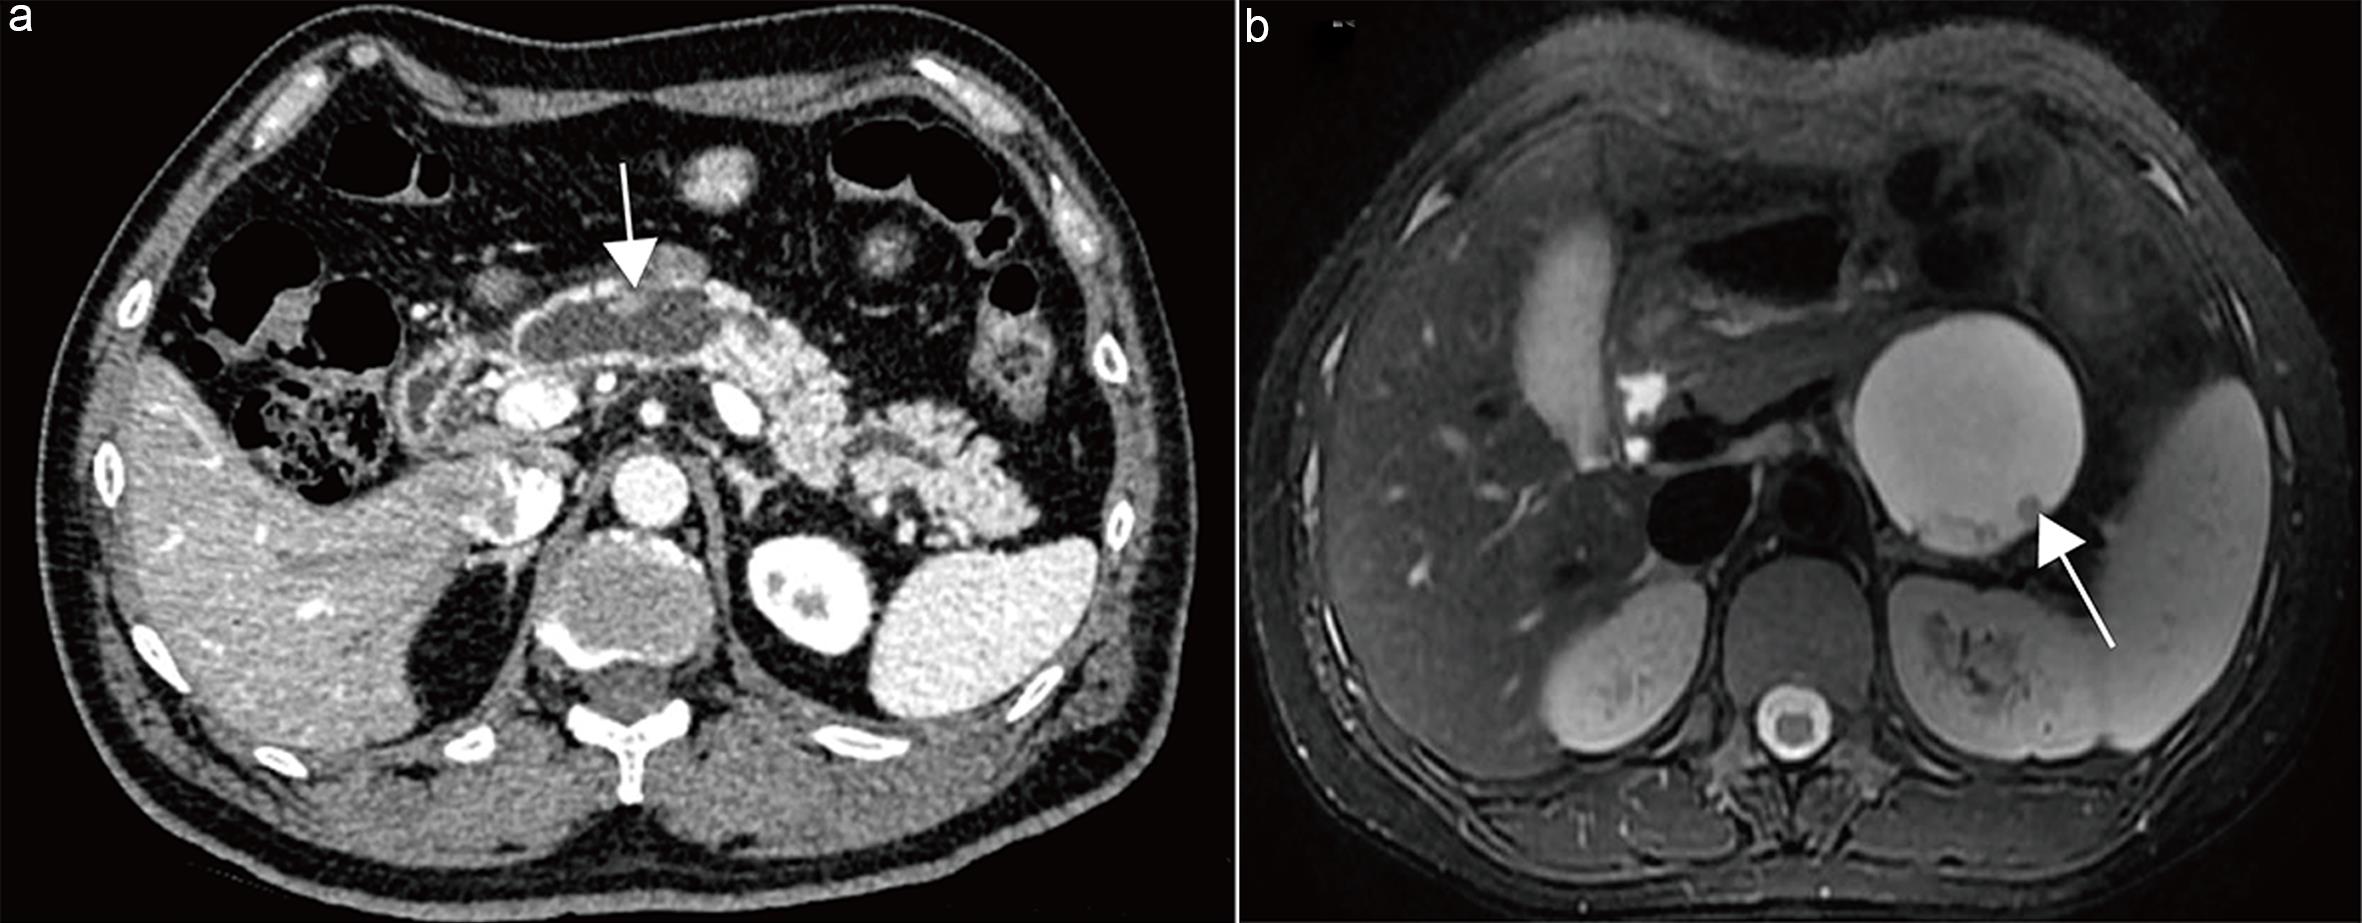

Recommendation 9: The maximal diameter of the main pancreatic duct should be measured on the optimal plane perpendicular to the long axis of the duct on MRCP, T2WI, or contrast-enhanced CT during the pancreatic parenchymal phase or portal venous phase.

Currently, there is no consensus on the measurement method for the main pancreatic duct. Based on existing literature,40–42 this guideline recommends measuring the maximal duct diameter on MRCP, T2WI, or contrast-enhanced CT during the pancreatic parenchymal or portal venous phase, selecting the plane perpendicular to the duct’s long axis (Fig. 5).

Methods for measuring the main pancreatic duct (MPD) diameter.

Fig. 5  Methods for measuring the main pancreatic duct (MPD) diameter.

(a) Main-duct intraductal papillary mucinous neoplasm (MD-IPMN). computed tomography (CT) curved planar reformation shows the optimal plane for measurement and the maximal diameter of the dilated MPD. (b) Main-duct IPMN. MR cholangiopancreatography (MRCP) shows measurement of the maximal diameter of the dilated MPD.